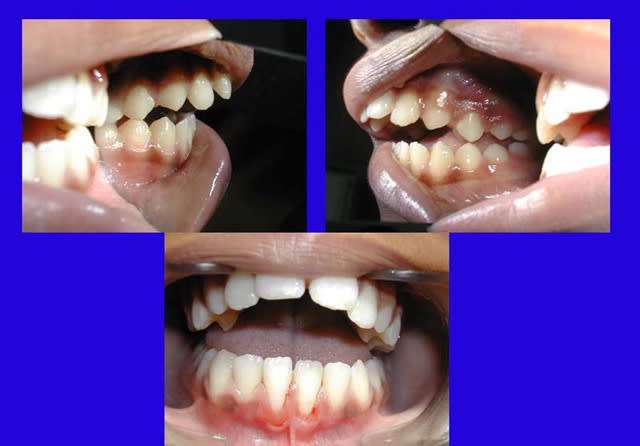

bjc,je reviens sur le cas que tu présente le 25 mars :peux tu detailler ce qui s'est passé entre les tps 1 et 2:quelles phases de traitement,combien de tps,et bien sur,peut être bientôt ,nouvelle rx

chakour Ecrivait:

-------------------------------------------------------

> bjc, je reviens sur le cas que tu présente le 25

> mars : peux tu détailler ce qui s'est passé entre

> les temps 1 et 2, quelles phases de

> traitement, combien de temps, et bien sûr, peut être

> bientôt, nouvelle radios ?

> ..

La fermeture de cette béance est effectivement impressionnante, surtout avec une telle proalvéolie au départ quand on sait qu’il n’extrait jamais.

bjc, pourrais-tu nous montrer ce traitement en détail ? Avec des photos latérales montrant les rapports molaires et des radios, ce serait bien. Merci d’avance.